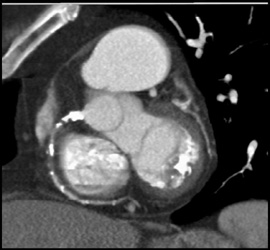

High Agatston Score